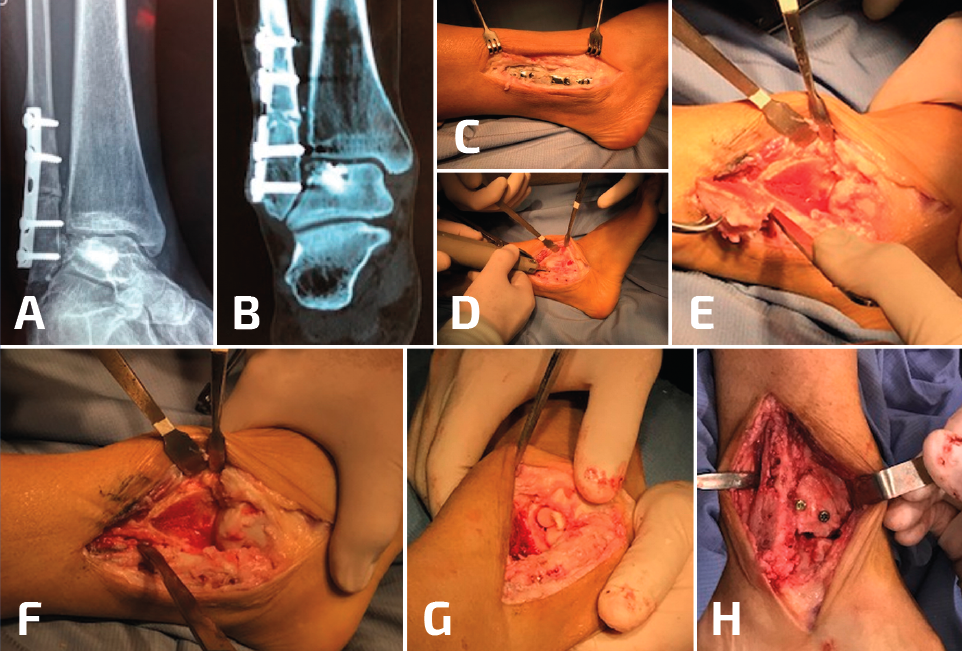

La selección de la osteotomía y el tipo de injerto para la reconstrucción va a depender de la posición de la mala consolidación; recuerden que el peroné puede estar acortado o rotado a externo, o bien acortado y rotado a interno. Idealmente, no sería necesario desprender la sindesmosis en su totalidad para elongar el peroné (Figura 3). Si el peroné está rotado hacia afuera y no está acortado, entonces se puede realizar una osteotomía rotacional sin elongación y, de esta manera, se preserva la sindesmosis, aunque esto no es una condición frecuente. El objetivo del tratamiento de la consolidación viciosa del peroné consiste en restaurar la correcta longitud y la rotación, para obtener una alineación anatómica del astrágalo dentro de la mortaja del tobillo. Sin embargo, también es importante reconocer otros aspectos del patrón original de la fractura.

Figura 3. En este paciente, además de la pseudoartrosis del peroné, se asocia un gran defecto osteocondral del astrágalo (A, B, C). Para acceder a la lesión, se realizó una osteotomía en la región lateral de la tibia (D, E, F). Después de la colocación de los injertos tomados de la rodilla, se realizó la osteosíntesis de la osteotomía de la tibia y posteriormente se trató la pseudoartrosis del peroné (G, H).

Cuando el ligamento deltoideo se encuentra elongado o lesionado, este debe ser reparado junto con la osteotomía correctiva del peroné, ya que solo el desbridamiento de la gotera interna no será suficiente para una buena corrección si el ligamento deltoideo está desgarrado. De igual modo, al reconstruir una fractura Weber de tipo C, la mala consolidación del peroné involucrará a la sindesmosis, que también debe ser movilizada, reducida y estabilizada para lograr la correcta reducción de la mortaja.